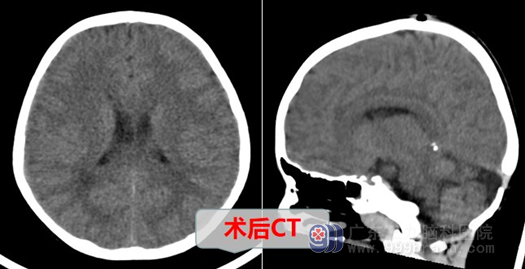

入院后经外十科欧阳辉教授团队,结合相关检查得出结论:患儿Ommaya管外露明确,拔除手术指征明确。术中注意要轻柔操作,保护好脑组织及血管,避免引起颅内出血。欧阳辉科主任指出:目前“1.Ommaya管外露;2.松果体成熟畸胎瘤切除术后”诊断明确。综合病情,有手术指征,如不手术,外露的Ommaya管会引起颅内感染,手术目的明确。必须尽行“Ommaya管取出术”,手术很快成功完成。

术后,小佳佳恢复情况良好,各项生命体征稳定,在经过几天的治疗后顺利康复出院。临走前小佳佳还在护士站对护士姐姐说:姐姐,姐姐,以后我不来找你玩啦,但是你要去我家来找我玩儿哦,我把我的小汽车送给你玩……小佳佳的童言童语惹得大家都一阵开心,我们感叹到:今天的阳光格外灿烂。